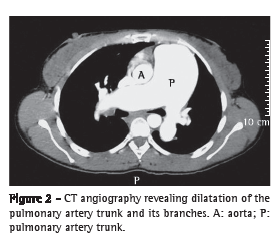

An ultrasound scan of the abdomen revealed moderate central and peripheral echogenic periportal thickening, gallbladder wall thickening, with signs of portal hypertension (portal vein = 13 mm and splenic vein = 10 mm), and an 11-mm paraumbilical vein as a pathway of collateral circulation, all of which are consistent with hepatosplenic schistosomiasis. The longitudinal diameter of the spleen was 117 mm. At the first assessment, upper digestive tract endoscopy revealed small-diameter esophageal varices. The serology was negative for hepatitis B surface antigen (HBsAg), antibody to hepatitis B surface antigen (anti-HBs), antibody to hepatitis B core antigen (anti-HBc), and antibody to hepatitis C virus (anti-HCV). A chest X-ray showed dilated pulmonary arteries and right heart enlargement (Figure 1), both of which were confirmed by chest CT (Figure 2). An electrocardiogram showed signs of right heart overload. An echocardiogram revealed right atrial and right ventricular enlargement, with an estimated pulmonary artery systolic pressure of 145 mmHg, as well as aneurysmal dilatation of the pulmonary artery (56 mm). The spirometry results were as follows: FEV1 = 2.22 L (76%); FVC = 3.04 L (90%); FEV1/FVC = 73.03%; and a negative bronchodilator test. The 6MWD was 153.6 m, and the test was interrupted, due to presyncope, at 75 s. Angiotomography and lung scintigraphy, which had been performed previously, revealed aneurysmal dilatation of the pulmonary artery, no pulmonary artery filling defects, and a low probability of pulmonary embolism. Right heart catheterization showed a pulmonary artery systolic pressure of 140 mmHg, a mean pulmonary artery pressure of 88 mmHg, a cardiac index of 3.0 L  min−1  m−2, and pulmonary vascular resistance of 23.0 Woods. Pulmonary vasoreactivity testing with nitric oxide was negative.

Data from facilities specializing in the treatment of patients with PH in Brazil suggest that schistosomiasis is the cause of the disease in at least 30% of such patients.(16) The clinical presentation seems to be similar to that of idiopathic PAH, being characterized by dyspnea on exertion, weakness, cough, palpitation, chest pain, and hemoptysis.(16) Chest X-ray usually shows dilatation of the pulmonary artery trunk and cardiomegaly due to right ventricular enlargement.(17,18)